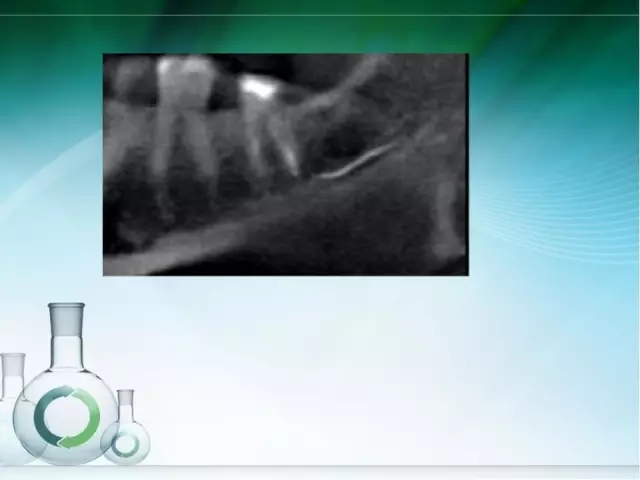

此文關(guān)鍵字:根管治療并發(fā)癥及處理